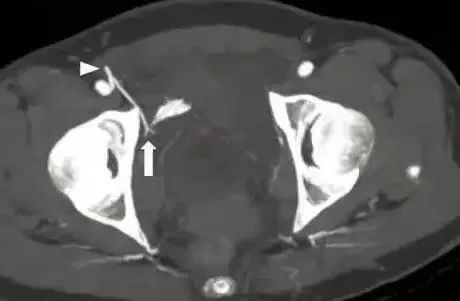

4.为动脉 5.为静脉

行CT,发现腹腔有10*10*15的血肿位于耻骨骨折旁边。

行血管造影后确定了为死亡之冠出血,后行血管栓塞闭孔动脉后,出血停止。一周后康复出院。